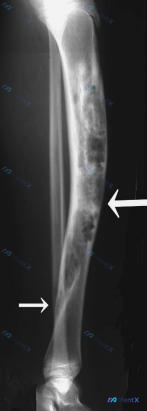

- X 光(14 岁及当前):胫骨骨干大范围溶骨性骨质破坏,呈膨胀性改变,骨皮质变薄,内部可见骨纹理消失及残留骨嵴(多房样改变)。侧位片可见胫骨前侧软组织轮廓向外膨出。